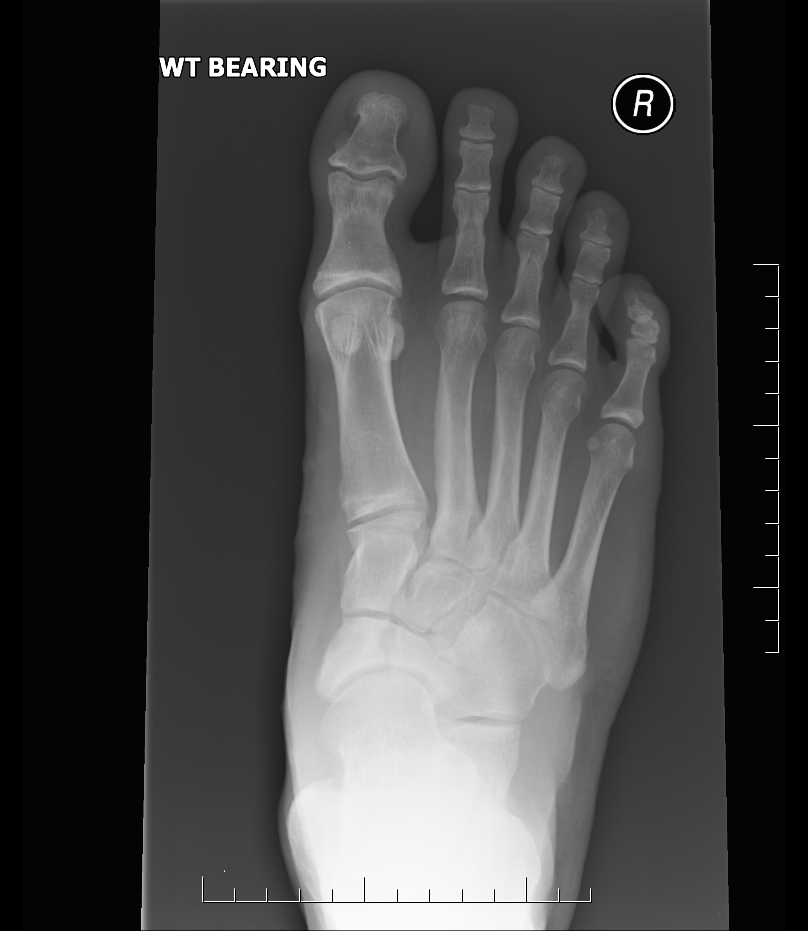

Navicular bone fracture on the xray. Trauma from falling of a scooter Avulsion Navicular Fracture mechanism of injury varies from forced inversion and plantar flexion in dorsal avulsion fractures to distinct “nutcracker” compression forces depending on the. how are they classified? avulsion fracture, the most common fracture of the navicular, is often associated with ligamentous injuries and. tarsal navicular fractures are rare fractures of the midfoot that may occur due to. Avulsion Navicular Fracture.

Avulsion Fracture of the Navicular r/Radiology Avulsion Navicular Fracture By part of the navicular affected (body, tuberosity or avulsion). Describe the etiology of tarsal navicular fractures. how are they classified? avulsion fracture of the dorsal aspect of the navicular bone usually associated with talonavicular ligament injury. Review the treatment strategies and operative indications for tarsal. mechanism of injury varies from forced inversion and plantar flexion in. Avulsion Navicular Fracture.